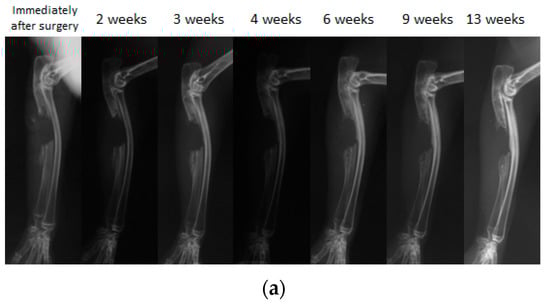

Because biodegradable synthetic polymers can degrade through hydrolysis and get absorbed in vivo, synthetic polymers are gaining popularity as scaffold material for bone regeneration. We have previously developed and reported on a biodegradable polymer that combines poly lactic acid-p-dioxanone-polyethylene glycol block copolymer (PLA-DX-PEG) and rhBMP-2, and observed its biodegradable properties in vitro (Figure 5). The PLA-DX-PEG implant was combined with rhBMP-2 to produce a composite implant, and we observed ectopic bone formation in the dorsal fascia of a mouse model [79]. In addition, we produced a critical-size bone defect in the ulna of a rabbit and transplanted a PLA-DX-PEG implant containing rhBMP-2. The implants were implanted in 1-cm-distance rabbit ulnar bone defects, and these defects were examined after 2, 3, 4, 6, 9, and 13 weeks using radiographical methods. In the control group with defects that were not filled with the implant, the defects were not repaired at three months postoperatively (Figure 6a). The bone defects were also not repaired in the group with PLA-DX-PEG implants alone (Figure 6b) and the group with PLA-DX-PEG implants combined with a small quantity of rhBMP-2 (Figure 6c). In the group with PLA-DX-PEG implants with a large quantity of rhBMP-2, the bone defect was repaired at two months (Figure 6d). Because PLA-DX-PEG implants alone have low osteoconductivity, signaling molecules such as rhBMP-2 are required to repair large bone defects. Using a PLA-DX-PEG implant as a scaffold, we observed that the repair of the bone defect and its strength are dependent on the dose of rhBMP-2.

A simple radiographic image of a rabbit ulnar bone defect model. (a) A bone defect was created and nothing was filled in the defect. Even 13 weeks after surgery, the defect was not repaired despite the formation of small new bone that was observed in the bone stump. (b) Only the PLA-DX-PEG implant was filled in the bone defect. At three weeks after surgery, formation of new bone from the bone stump was observed. At six weeks after surgery, the new bone from the distal stump showed bony union with the rib. Even 13 weeks after surgery, the bone defect resulted in a non-union with no cross-linking in the new bone. (c) The bone defect was filled with a PLA-DX-PEG implant combined with 10 μg rhBMP-2. Although formation of new bone from the bone stump was observed, the bone defect of the ulna resulted in a nonunion at 13 weeks after surgery without any cross-linking in the new bone. (d) The bone defect was filled with a PLA-DX-PEG implant combined with 100 μg of rhBMP-2. Three weeks after surgery, the bone defect was cross-linked by the newly formed bone from the bilateral bone stumps. Nine weeks after surgery, there was formation of new bone in the bone defect that developed into mature bone with trabecular structure.